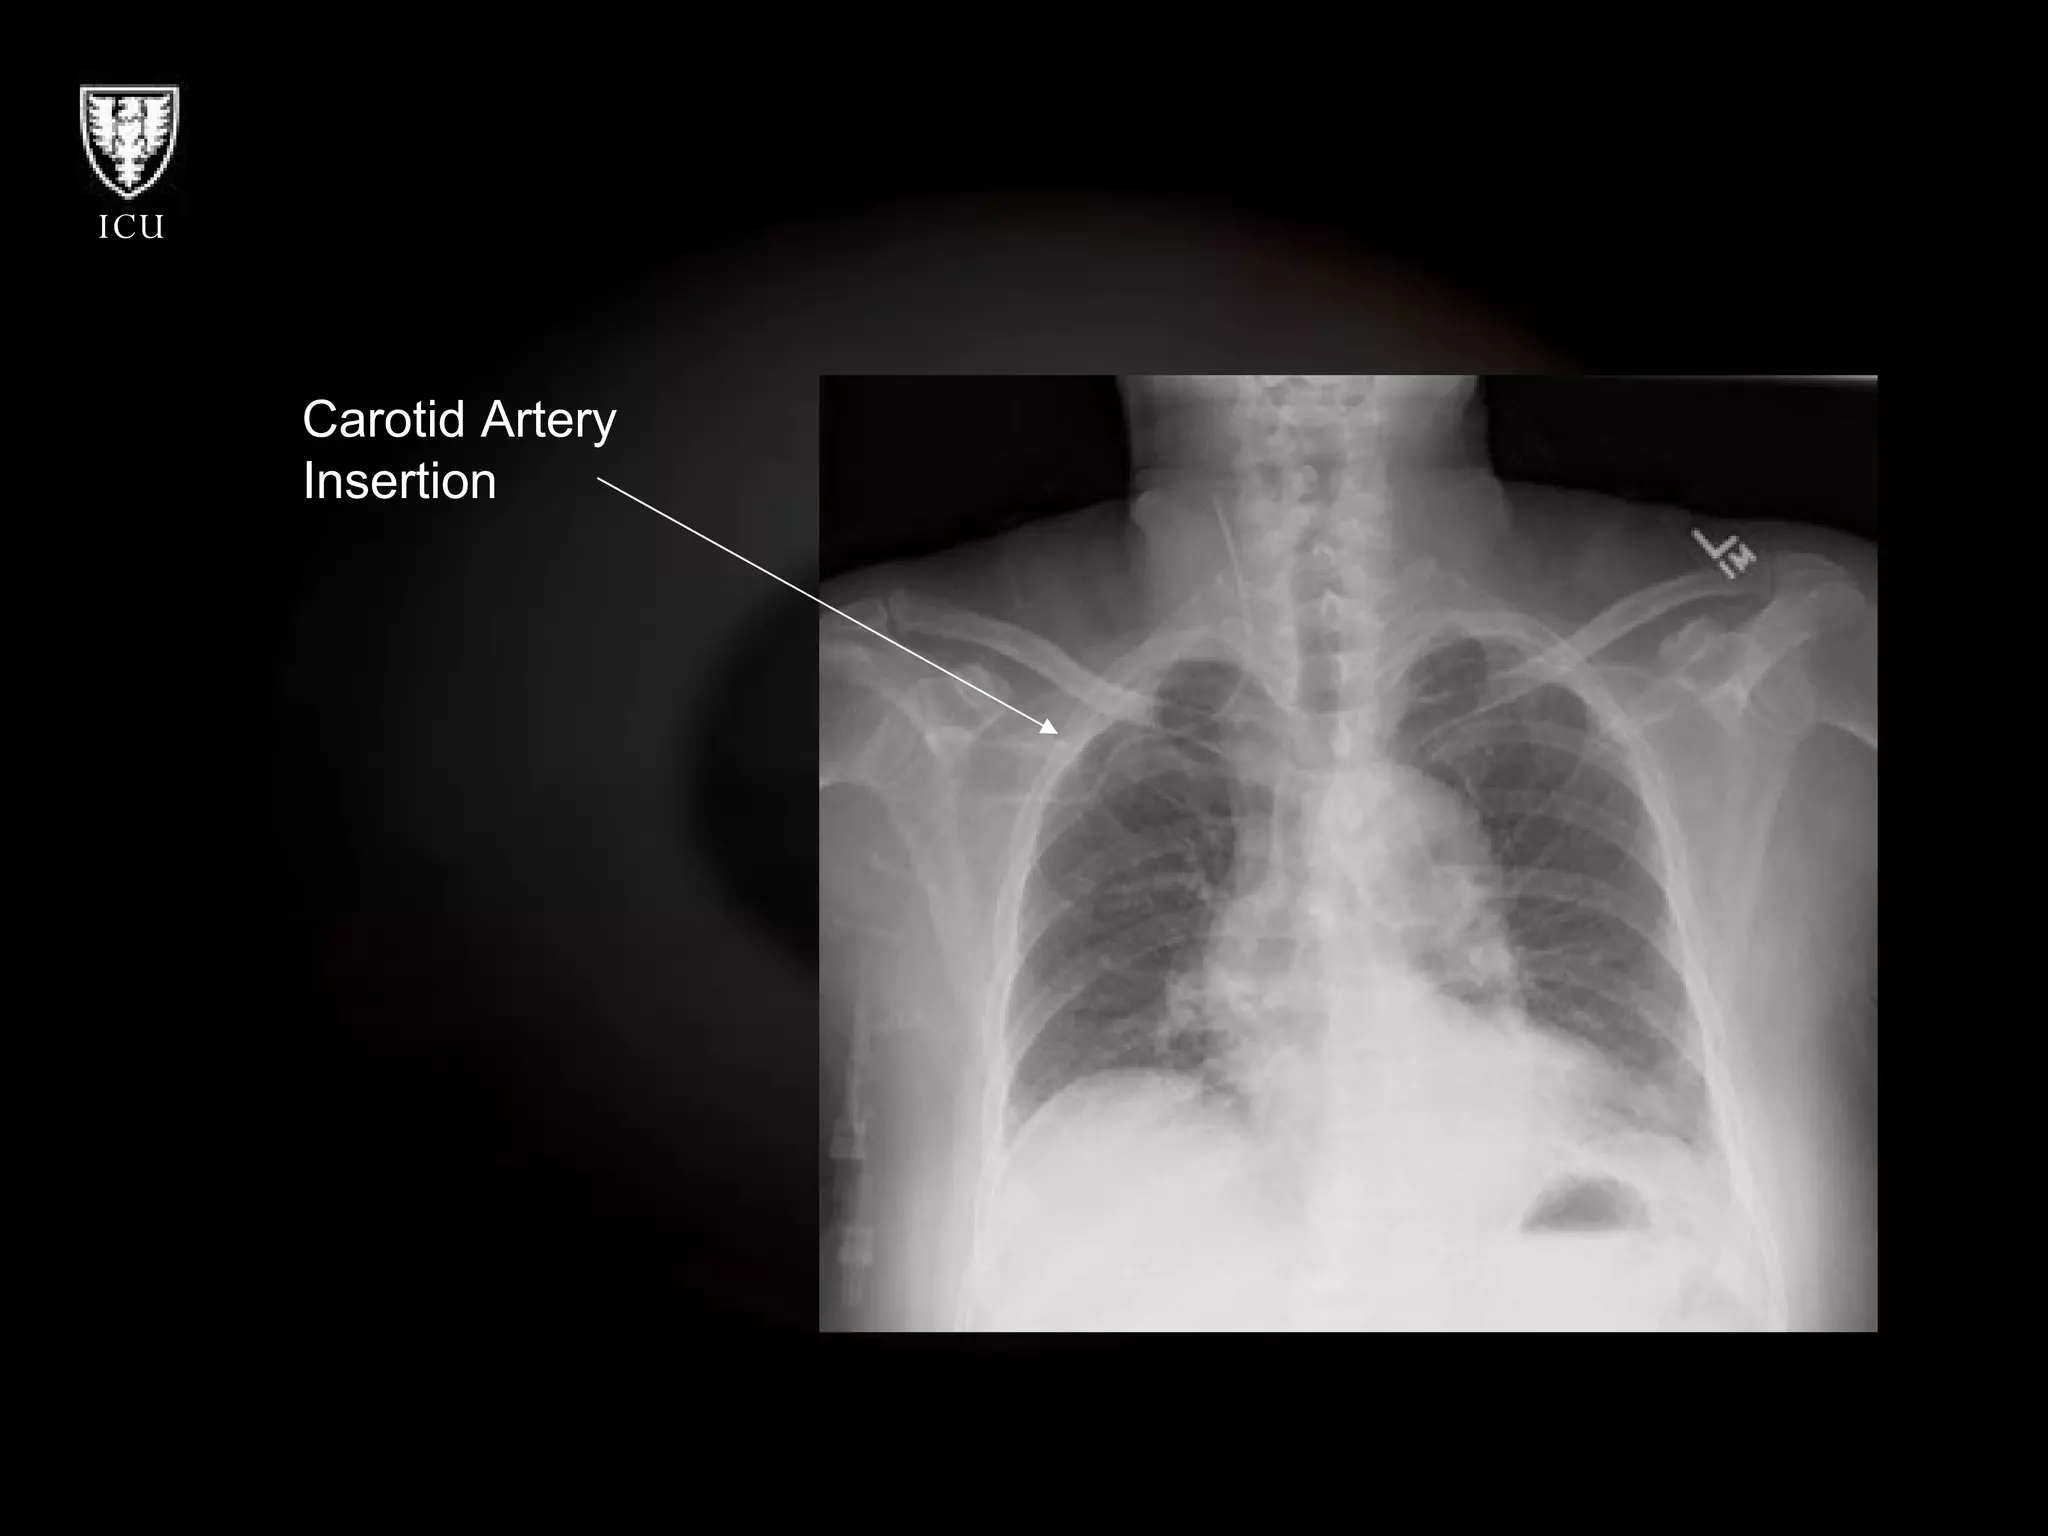

Carotid Artery  Insertion